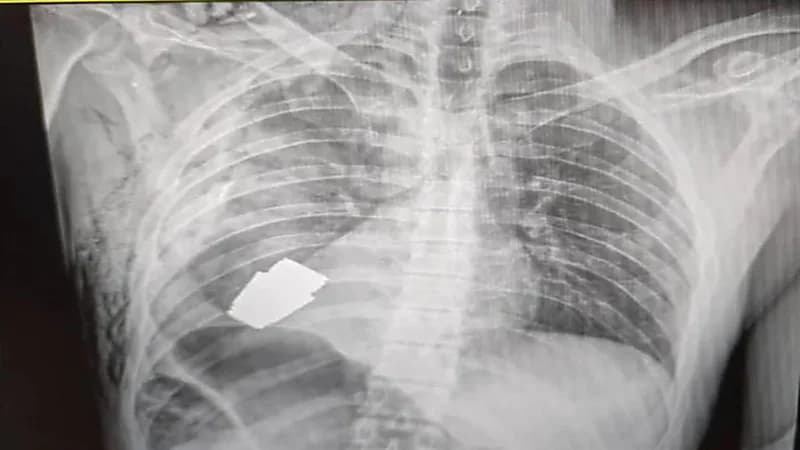

نجح جرّاح عسكري في إزالة قنبلة حية استقرت داخل جسد جندي أوكراني وعرضت حياته للخطر إذ إنها يمكن أن تنفجر في أية لحظة.

وقال حاكم منطقة باخموت الأوكرانية، سيرهي بورزوف، إن الأطباء العسكريين أجروا عملية جراحية لإزالة القنبلة غير المنفجرة من جسد الجندي.

وأبان أن إزالة القنبلة اليدوية تمت بنجاح، وجرى إرسال الجندي المصاب لإعادة التأهيل والتعافي.